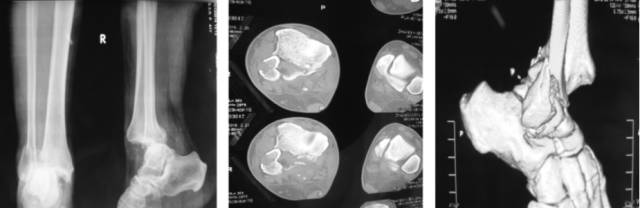

Pilon骨折

是指胫骨远端关节内骨折,常常由垂直暴力所致,常常合并腓骨骨折和严重的软组织损伤。